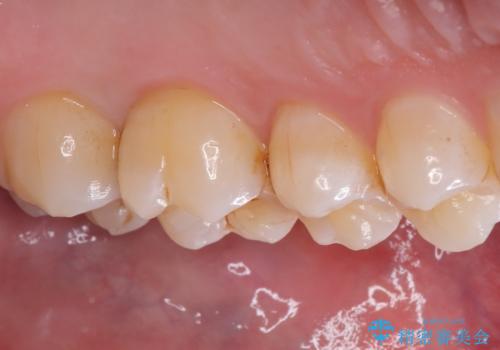

左上6番の歯には元々修復物が入っていましたが、それも一度除去し新たにMOD窩洞のセラミックインレーをセットしました。

左上7番咬合面裂溝の着色部分は今後エアフロー等を使用し落としていく予定です。

セラミックインレーセット時はラバーダム防湿を行っています。